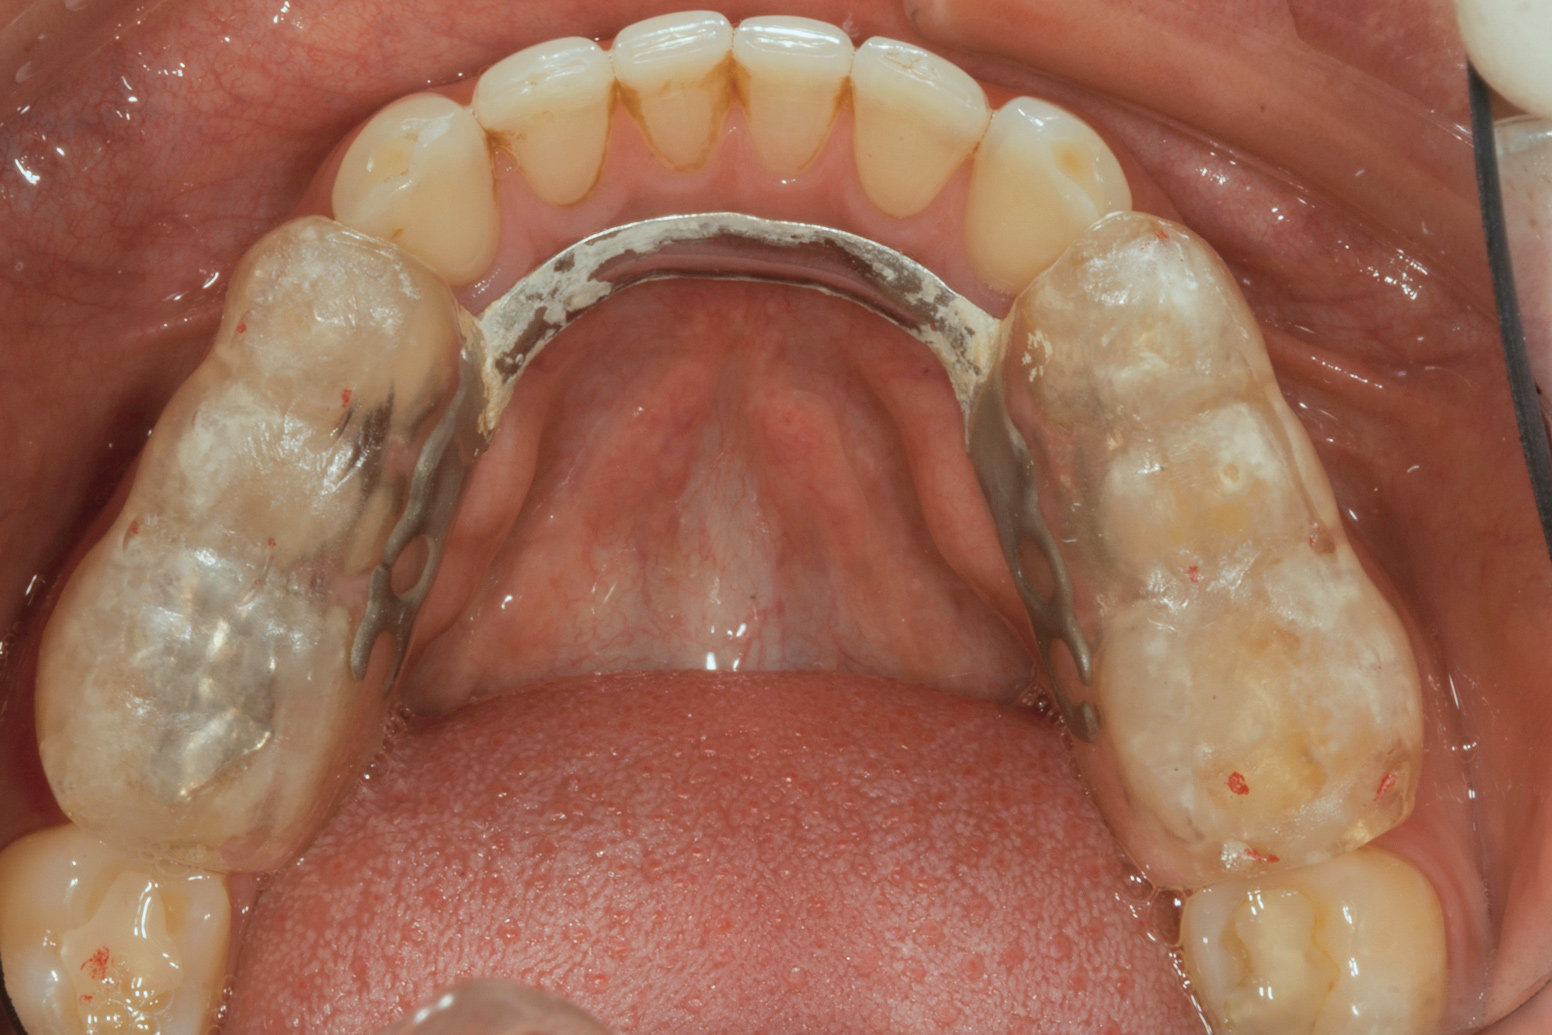

(3.) Preoperative occlusal view of lower arch with orthotic in place.

Figure 3

Ultimately, the patient developed joint and muscle symptoms due to his lack of posterior support and sought the help of a specialist. His bite was analyzed, and he was fitted with a dental orthotic that allowed his teeth to touch in centric relation (Figure 3). This was intended to be a temporary measure to stabilize the patient's bite and make him comfortable, but before any permanent treatment could be carried out, he moved abroad and had been living with the device for more than four years before the time of the consultation. He stated that his bite was now very stable with the orthotic, but he was looking for a more permanent solution and also wanted to improve the overall appearance of his smile.

The patient's removable dental orthotic covered the lower bicuspids and first molars. With the orthotic in place, there was shim stock contact on all posterior teeth and on the second molars that were not covered by the appliance. However, there was no incisal overlap and a lack of anterior guidance.11 When the orthotic was removed, solid shim stock contacts were present on the second molars and the right lateral incisor. These contacts were reproduced every time the appliance was removed. The same contacts were found on the patient's mounted models, which confirmed that the joints were in centric relation. Whether the lower second molars had overerupted as a result of wearing the appliance or had already been in this position before the orthotic was fitted could not be established. Apart from these three contacts, no other teeth touched, and there was a 2-mm space between the posterior teeth, making mastication difficult. Interestingly, wear facets were present on the palatal surfaces of the upper central and lateral incisors, indicating that at some point in time, there had been significant overlap of the anterior teeth and a possible constriction of the chewing envelope. Analysis of a cephalometric radiograph showed a class II growth tendency with a reduced mandibular plane angle, which supported the theory that the patient had at one time possessed a class II occlusion.

The patient's bite was obviously unsatisfactory, but with the orthotic in place, he was completely symptom-free and stable, and therefore, considered to be in acceptable function. However, he was considered to be in occlusal dysfunction without it because he lacked simultaneous, equal intensity posterior contacts. Deprogramming the patient and confirming centric relation was not considered to be required at this stage because as soon as he removed the orthotic, his occlusal situation was similar to wearing a tripod deprogrammer with only one anterior and two posterior contacts, and these had been confirmed to be reproducible every time when checked intraorally and on the mounted models (Figure 5). The use of a Kois Deprogrammer is one way to obtain centric relation, but other ways, such as bimanual manipulation or the use of a Lucia jig, a leaf gauge, a bite plane, or an occlusal splint have been discussed by various authors.14